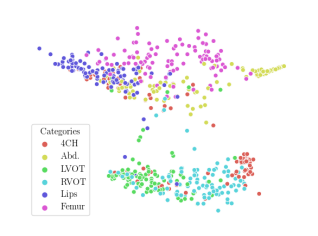

We compare the -distance of categorical features and domain features. Fig. 5 (a) shows that domain difference is higher in domain features than in categorical features. This indicates that domain features contain more domain information whereas categorical features are more domain-invariant. Fig. 6 shows the t-SNE plot of categorical features in both domains for MIDNet. From Fig. 6 (a), we observe that the categorical features learned by MIDNet enable the anatomical classification. Fig. 6 (b) shows that the learned categorical features are domain-invariant.

In addition, we utilize t-SNE plots for feature visualization in Fig. 10. Comparing Fig. 10 (a) and Fig. 10 (b), we observe that with mutual information disentanglement, (1) samples from the same category are more tightly clustered (see the top row) and (2) the source domain and the target domain are overlap more (see the bottom row). This indicates that mutual information disentanglement is important for learning categorical-focused and domain-invariant features. Fig. 10 (a), (c)-(d) show that the proposed method outperforms other state-of-the-art methods for learning category-discriminative and domain-invariant features, especially for unseen categories in the target domain (e.g., (a) vs. (d)).